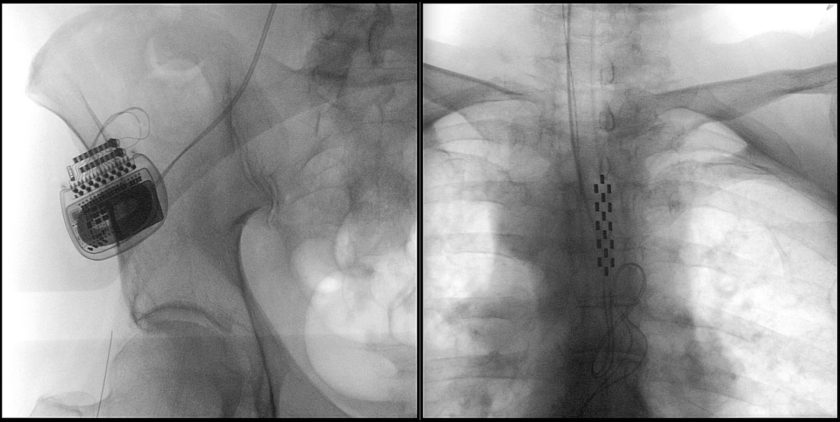

Los especialistas describen el estimulador cerebral profundo como una especie de marcapaso que produce una alteración al nivel del circuito afectado. “Cuando uno apaga el estimulador se acaba la lesión y el paciente vuelve a estar como estaba antes. Puedes aumentar el voltaje, la cantidad de polos que se está estimulando y se mantiene al paciente mucho más tiempo porque la enfermedad sigue progresando y uno puede ir manipulando la estimulación, aumentándola”, asegura el Dr. Pedro Vázquez, neurocirujano del Hospital Clínico Universidad de Chile José Joaquín Aguirre.

Tanto para hospitales públicos como clínicas privadas el costo de la cirugía no es una barrera menor. Sólo el estimulador cuesta alrededor de 20 millones de pesos y su aplicación no cuenta con políticas públicas que faciliten su accesibilidad. Ni las isapres ni Fonasa la cubren. En la mayoría de los casos los propios pacientes deben costear el dispositivo y, algunas veces, los centros médicos, empresas u otras organizaciones se encargan de respaldar la inversión. “En nuestro país lo que necesitamos más urgentemente es un proyecto de financiamiento estatal para la enfermedad de Parkinson. La estimulación cerebral profunda actualmente es el estándar de tratamiento para un subgrupo de pacientes. Esos pacientes debieran tener una forma de financiamiento estatal”, sostiene el Dr. Carlos Bennett, neurocirujano pediátrico del Hospital Van Buren.

Así también lo destaca el Dr. Valdivia: “En el Parkinson es un tratamiento estándar desde el 2002 en la FDA (Administración de Alimentos y Medicamentos) y 1998 en el EMA (Agencia Europea de Medicamentos). Se instalan aproximadamente más de 15 mil al año en todas partes del mundo”. La masividad internacional del procedimiento es tal que para muchos ya es hora –hace tiempo– de expandirla en nuestro país, donde pacientes potenciales y el equipo profesional para atenderlos existe, pero lamentablemente el dinero estanca el desarrollo.